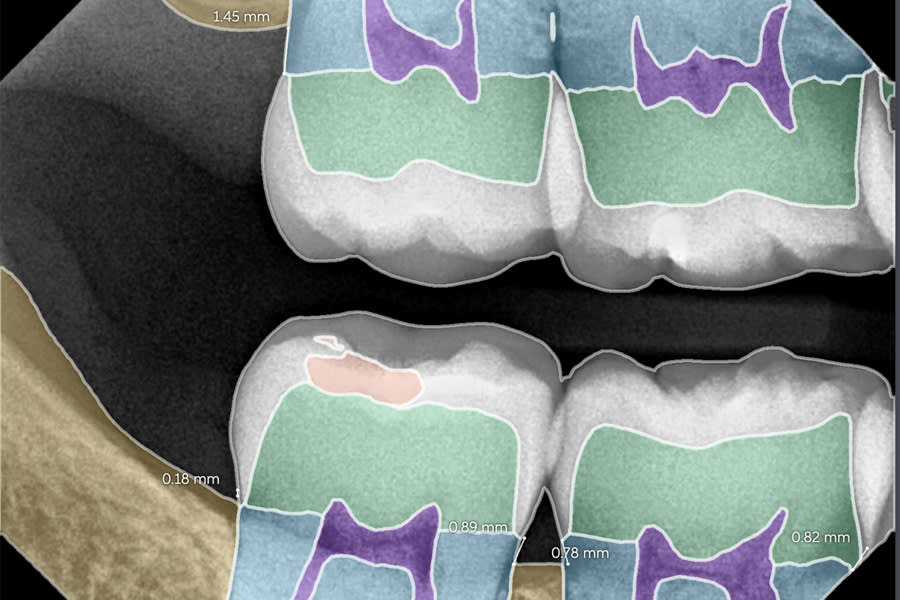

Case 2: Liam (Adolescent Patient, AI-Detected Lesions)

Liam, a 13-year-old male patient, had a lax diet typical of many adolescents, limited flossing, and only moderate home care. Despite nutritional counseling and home care instruction, AI-assisted imaging revealed incipient lesions on the distal aspect of tooth No. 14 (with No. 15 erupting) and the distal of tooth No. 19.

After cleaning, etching, and drying was performed, Curodont was applied, followed by application of fluoride varnish and adjunctive use of fluoride mouthwashes. AI-assisted imaging was used at baseline and at follow-up, supporting early detection and clear patient communication.

At follow-up visits, lesions were no longer detectable with AI or radiographically. Both patient and parent appreciated avoiding operative care, particularly given the challenges of isolating tooth No. 14 during eruption of No. 15. This case demonstrates the synergy of AI diagnostics with non-invasive therapy, shifting treatment from “watch and wait” to proactive repair. (Figure 3 and Figure 4)